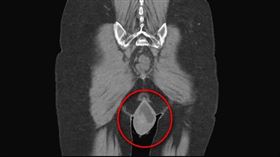

腹脹、貧血竟忍2年!婦子宮肌瘤大如籃球

一名44歲有蟹足腫體質的女性患者,數年前被診斷出多發...

她腹痛想吐 驚見超巨卵巢腫瘤 塞滿骨盆腔

一名50歲女病患一日晚上休息時,突然腹痛如絞,還伴隨...

驚!6旬婦頻尿2週 揪15cm「巨大卵巢癌」

小心婦癌之王!一位60歲的婦人連兩週有頻尿現象,原以...